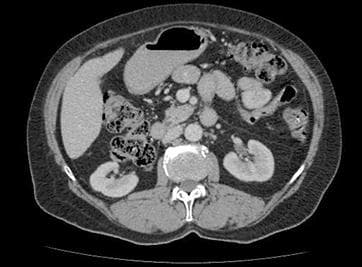

Detailed examination of the liver, pancreas, gallbladder, and kidneys with Upper Abdomen CT Scan. Advanced medical imaging center and radiology services for reliable results.